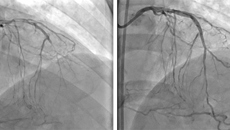

医学的深奥永无止境,每一个医生在他的行医生涯中,都会遇到生死难料的医学难题,到底应该前行还是止步?他心里的最大支持一定是来自患者。而当一个生死抉择摆在患者和他的亲人们面前的时候,能够和他们共担风险的也只有医生。 43岁的兰先生来自百色市平果县,1个月前因突发阵发性胸闷来到南宁某大型医院就诊。兰先生的阵发性胸闷颇为严重,每次持续近20分钟。入院检查发现,兰先生心脏右冠状动脉、左冠状动脉前降支、左...02.172016